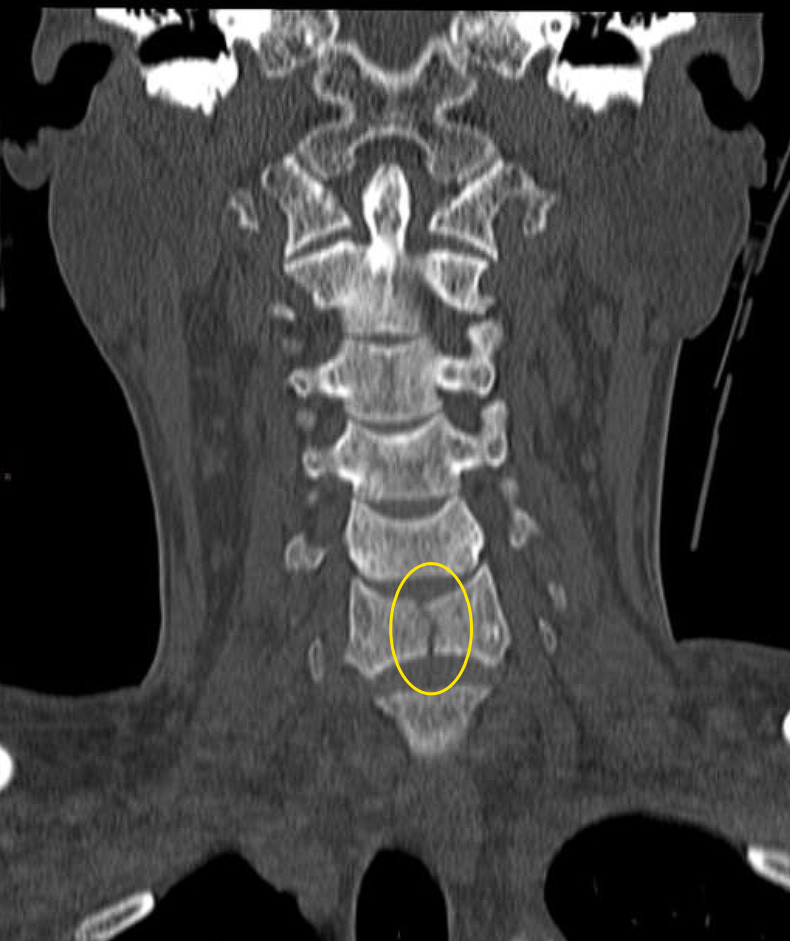

Outcome: A non-contrast cervical spine CT is ordered, revealing a C6 vertebral body fracture. Neurosurgery is consulted, and the patient remains in a cervical collar with follow-up arranged.

C6 vertebral body fracture on CT